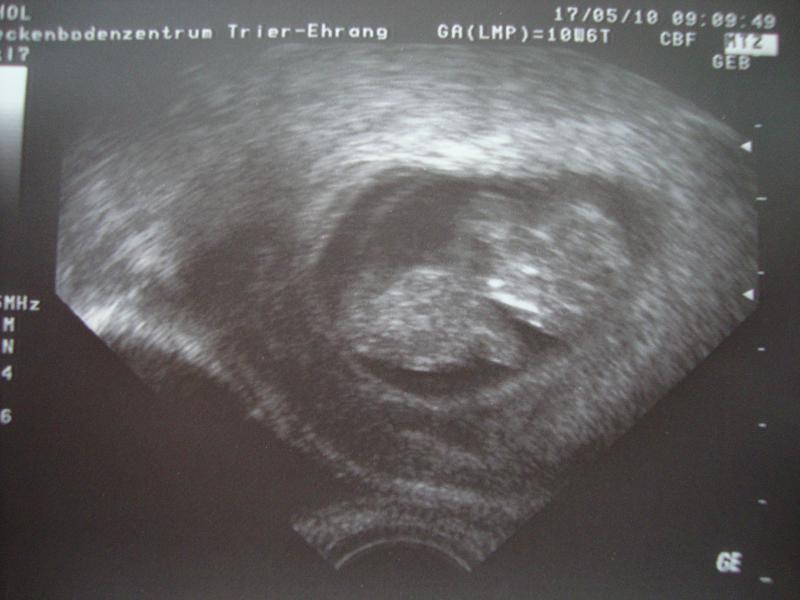

Es war ein riesiges Hämatom und die Gefahr war ziemlich groß dass entweder das Baby mit abblutet oder die Versorgung abgedrückt würde, weils direkt an der FH war, aber Hanni hat es zum Glück gut überstaden, wächst und gedeiht prächtig. Hoffe es bleibt jetzt so und ich kann einfach ganz normal schwanger sein. Nächsten Mittwoch hab ich wieder Termin bei meinem FA. Ich häng noch das neueste US-Foto an.

US Bild 20.05.2010 004kl.jpg